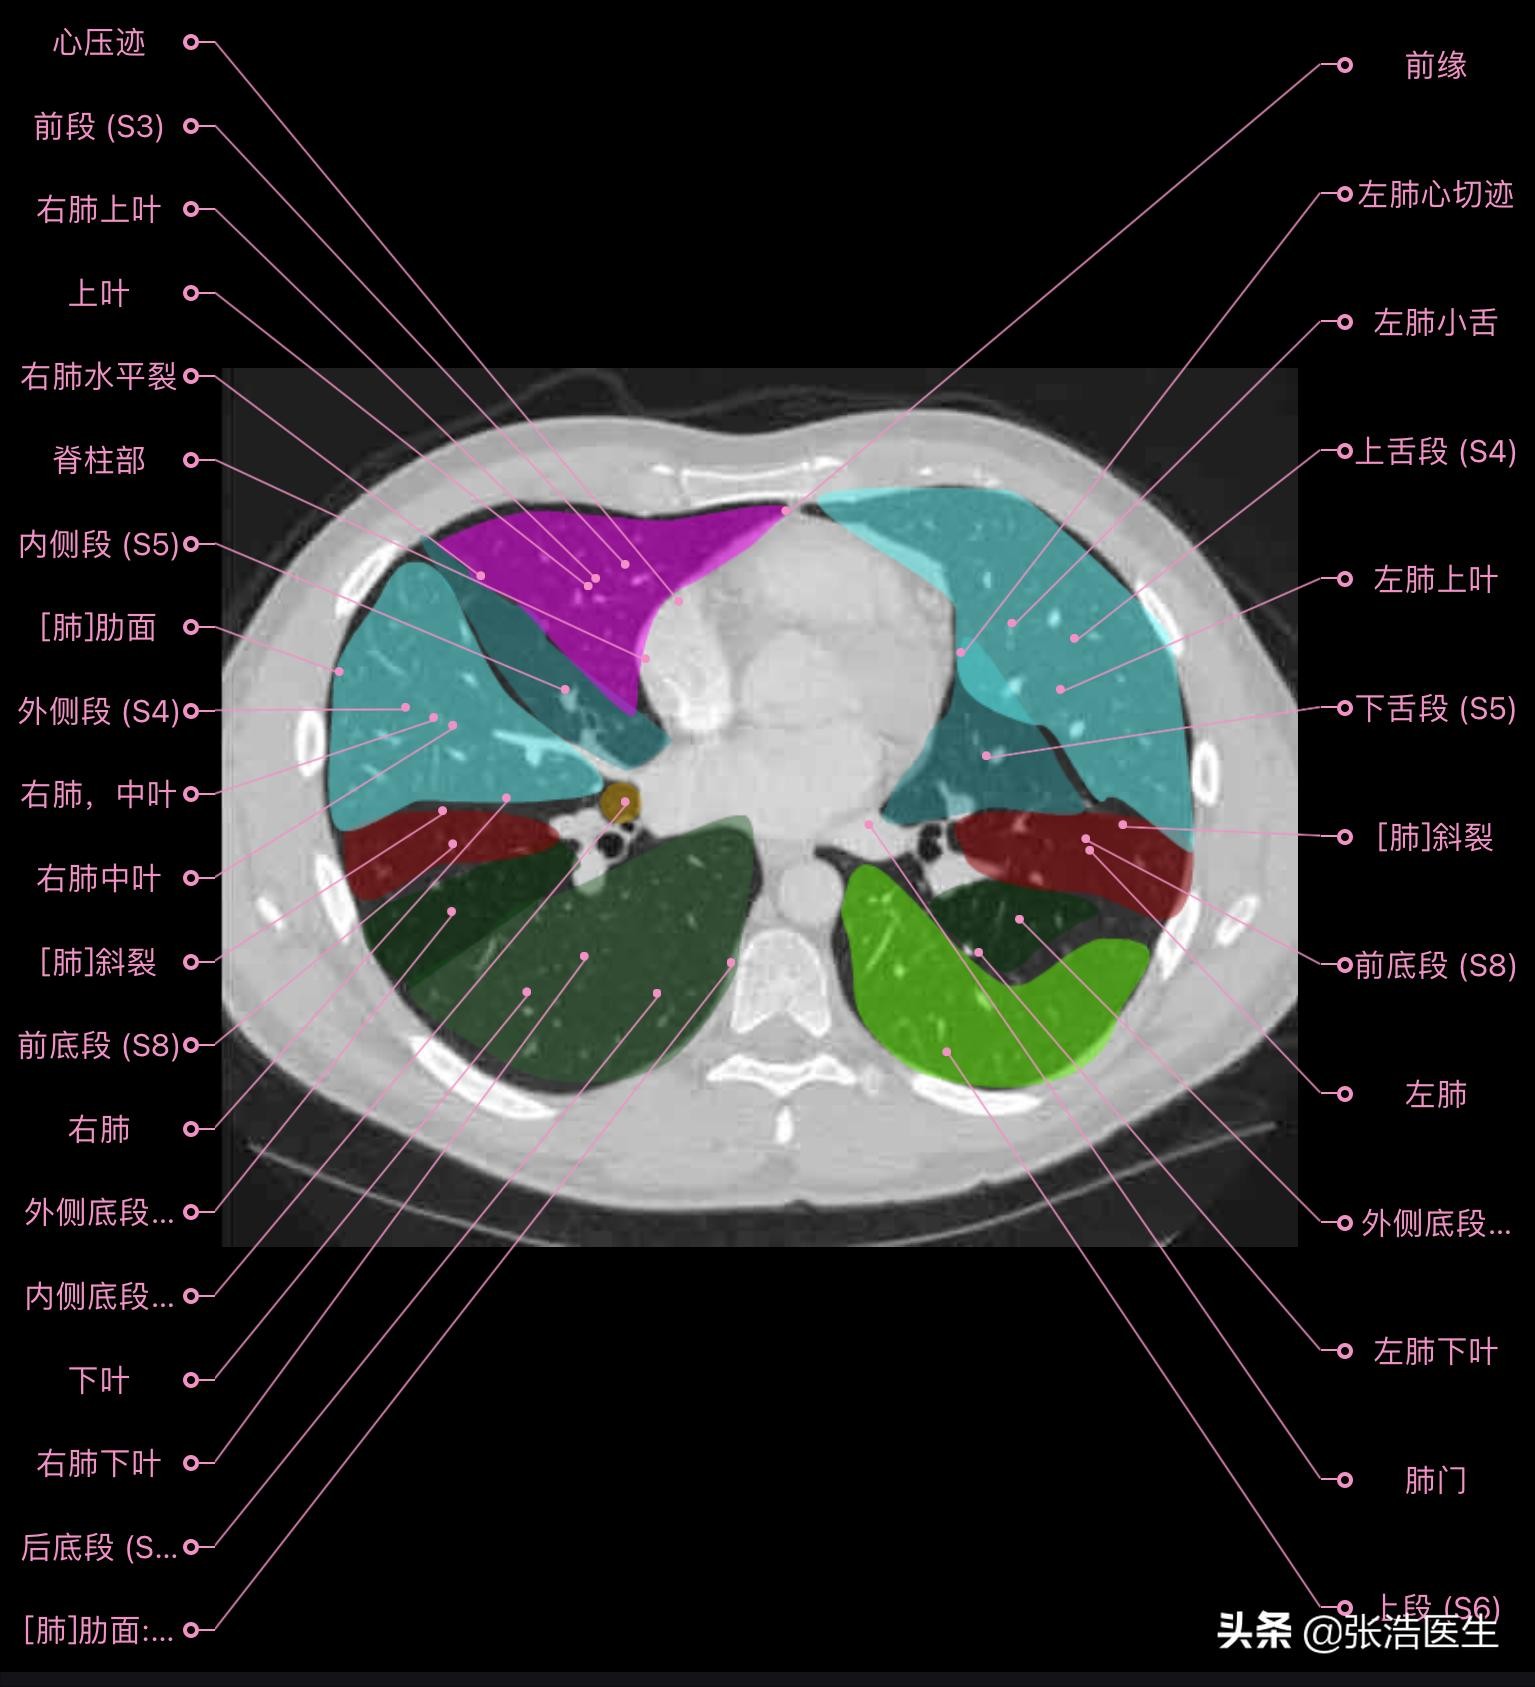

肺部CT横断面高清解剖图谱(图层3)

肺部CT横断面 高清解剖图谱

精选15层常用解剖断面

每一层都带有详细标注,值得收藏学习!